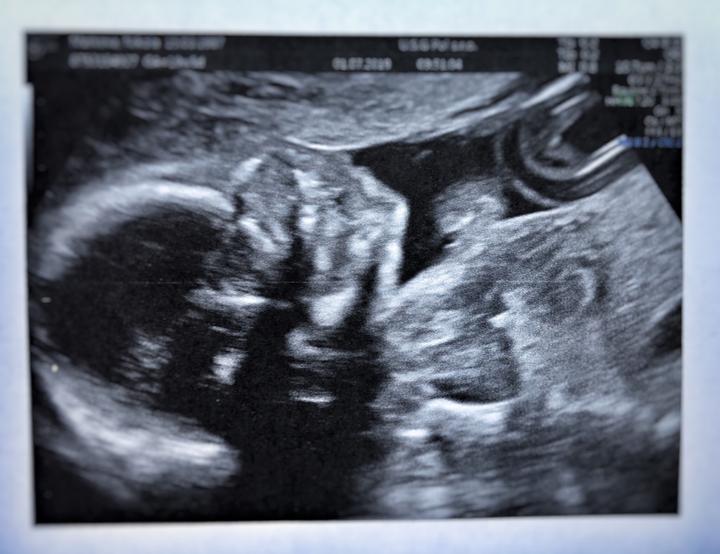

Tak v bříšku nosím princeznu🥰😍❤️👸🏼